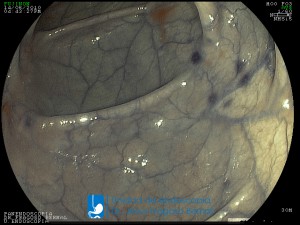

La Unidad de Endoscopía fue creada en 2002 por el Dr. Jesús Fragoso Bernal, es pionera en el estado por la utilización de la tecnología más avanzada, que nos permite ofrecer servicios integrales de diagnóstico y tratamiento para las enfermedades del aparato digestivo.